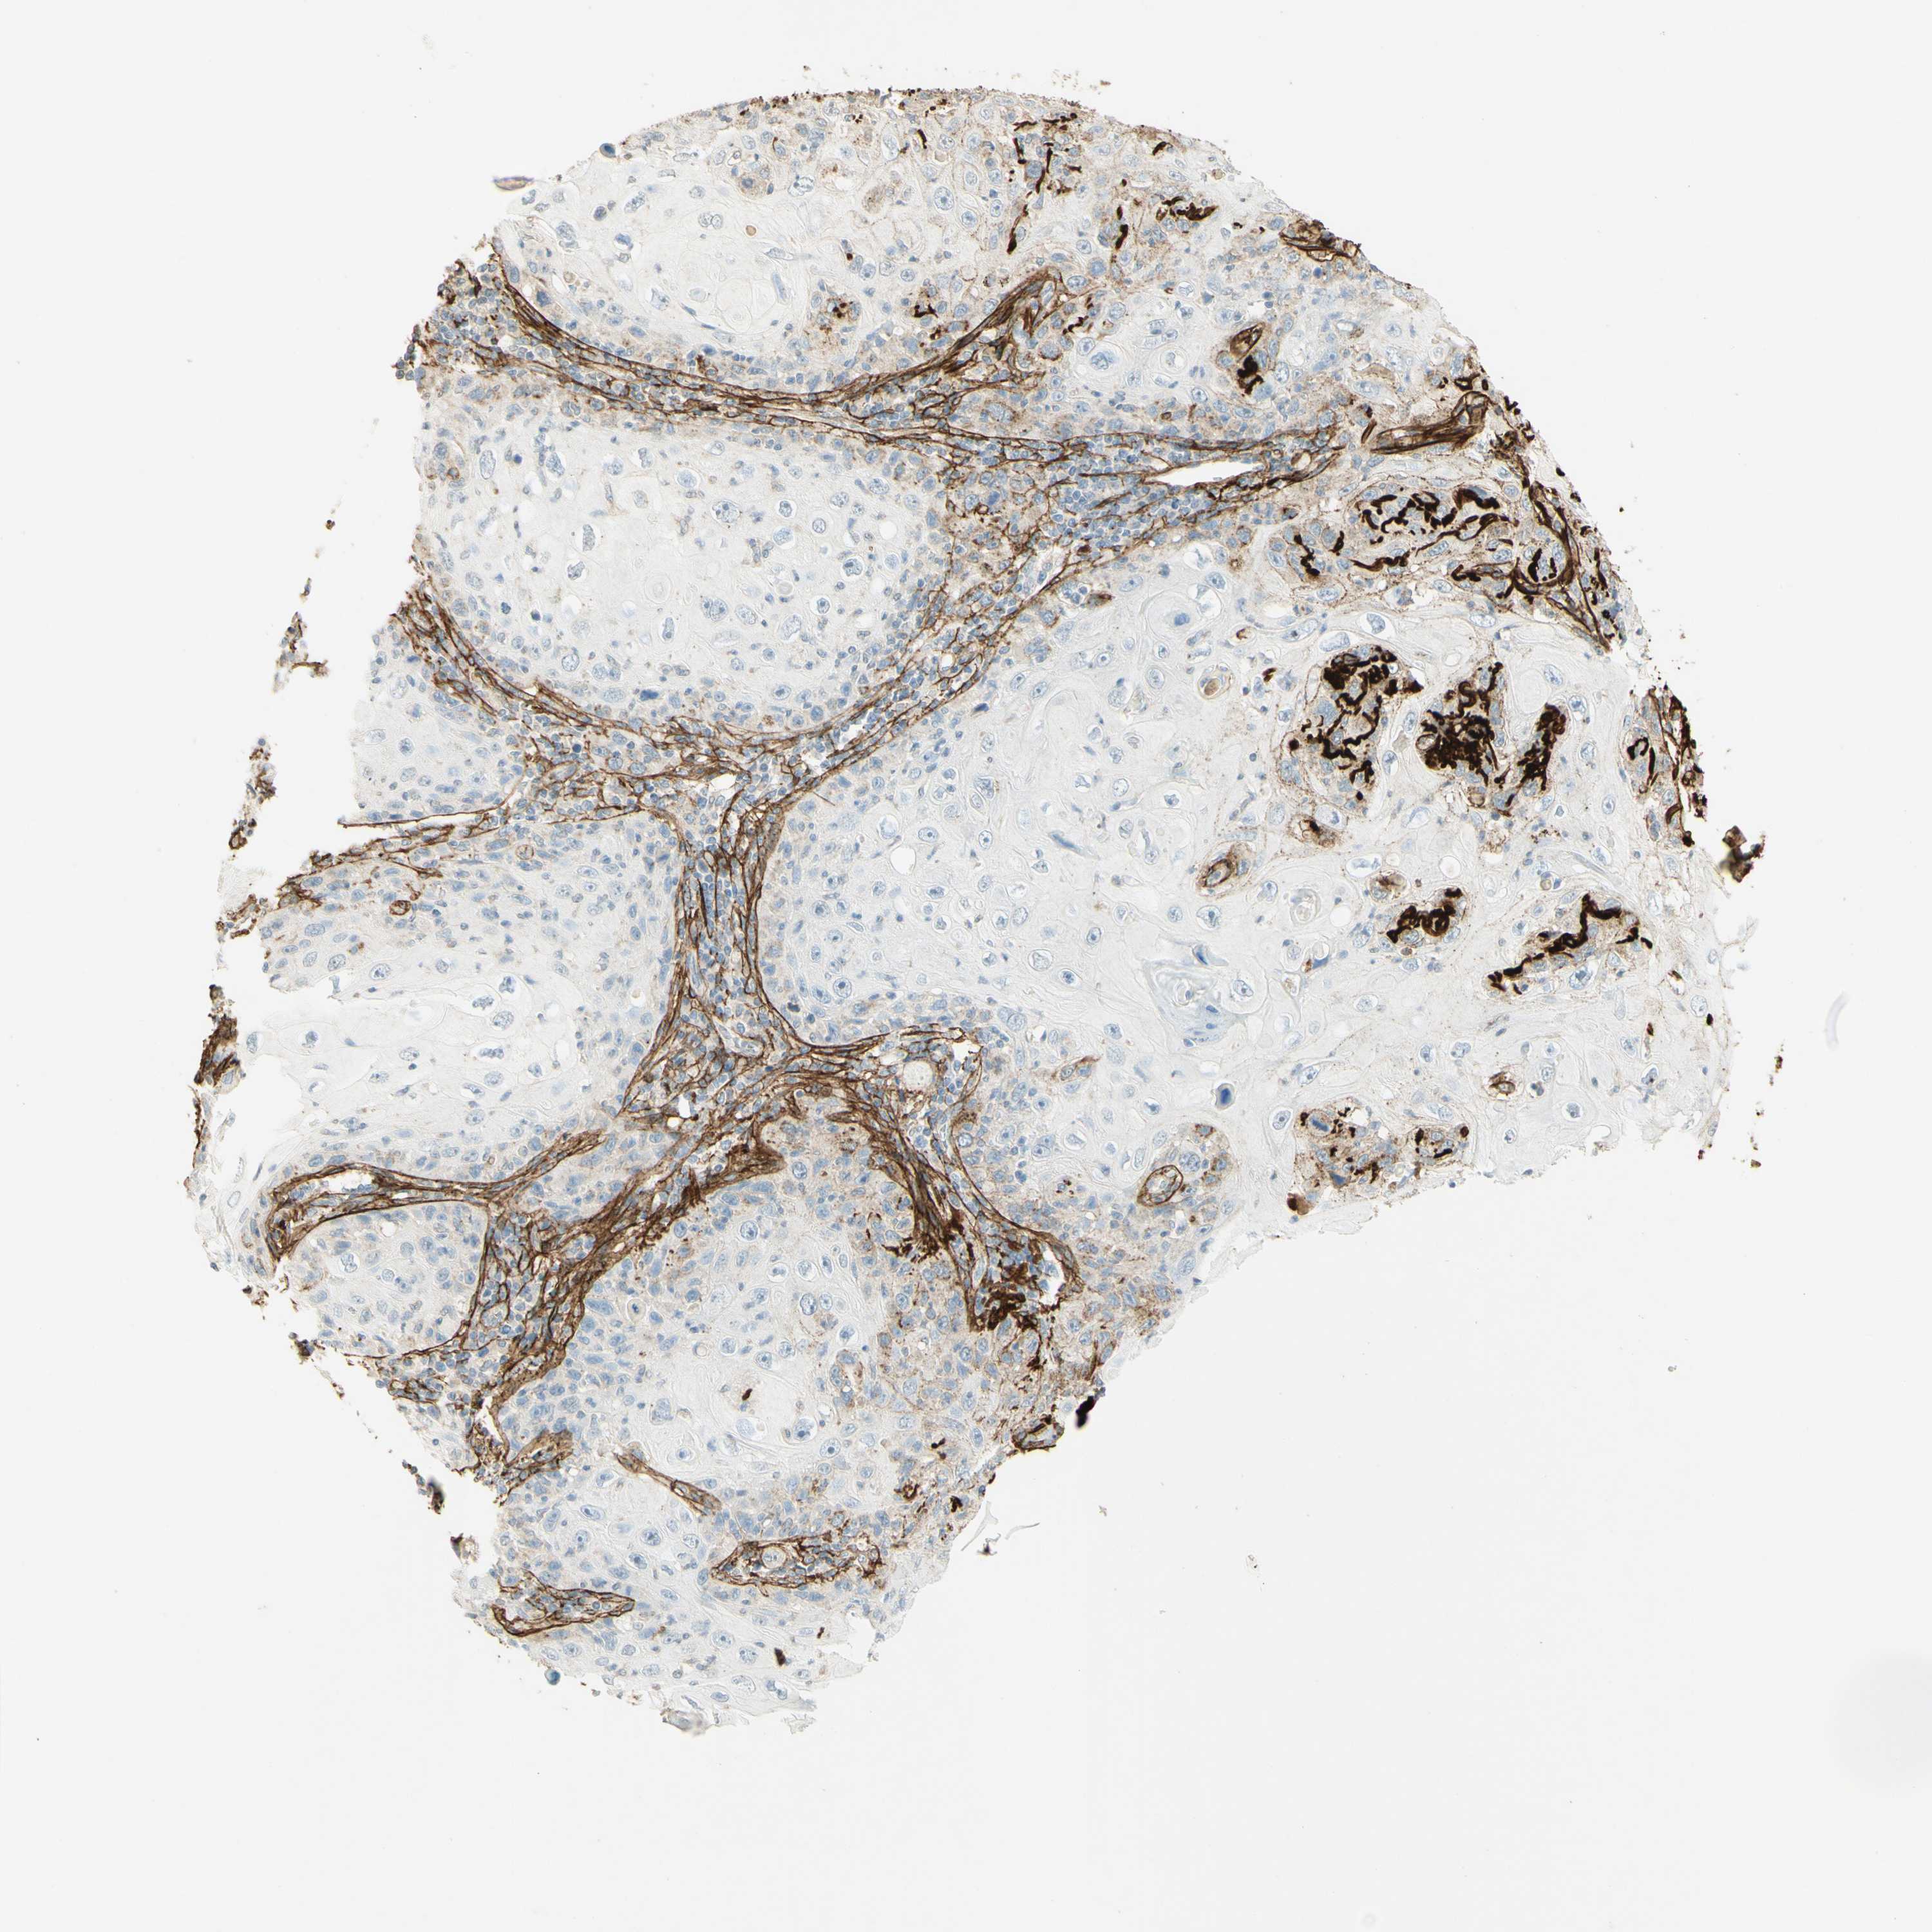

SKIN CANCER - Protein expressioni

A mouse-over function shows sample information and annotation data. Click on an image to view it in a full screen mode. Samples can be filtered based on level of antibody staining by selecting one or several of the following categories: high, medium, low and not detected. The assay and annotation is described here.

Antibody stainingi

Antibody staining in the annotated cell types in the current human tissue is reported as not detected, low, medium, or high, based on conventional immunohistochemistry profiling in selected tissues. This score is based on the combination of the staining intensity and fraction of stained cells.

Each image is clickable and will lead to virtual microscopy that enables deeper exploration of all samples and also displays staining intensity scores, fraction scores and subcellular localization as well as patient and tissue information for each sample.

Antibody HPA026726

Antibody HPA026764

Antibody CAB010907

Staining

High

Medium

Low

Not detected

Squamous cell carcinoma, NOS